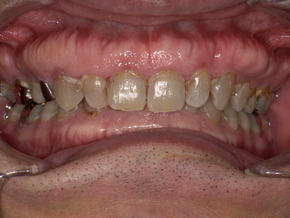

症例紹介(50代男性)

スリープスプリント装着後の口腔写真。下顎前方移動により気道が広がった状態